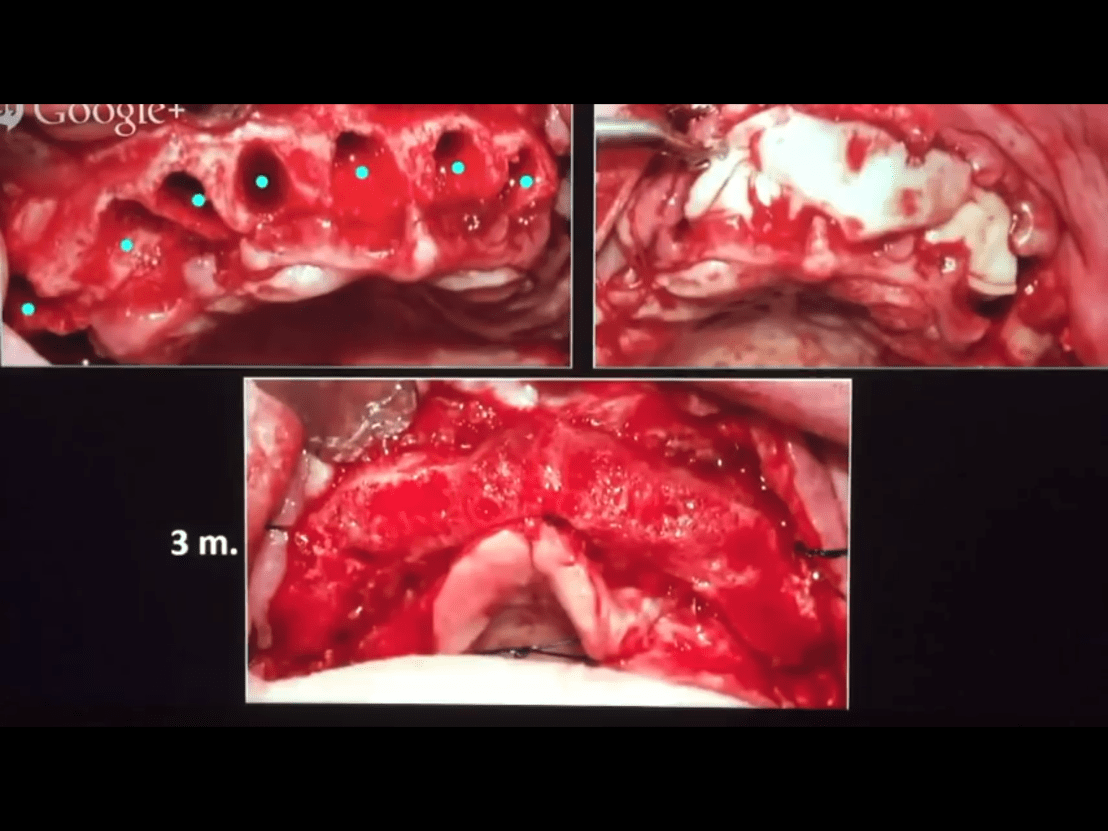

เช่น การทำ Sinus lift

การใช้เพื่อทดแทนขีดจำกัดของการใช้ Artificial membrane

จะเห็นว่า การเกิด Incision line opening ไม่เป็นปัญหาในกรณีนำ PRF membrane มาใช้แทน Goretex membrane